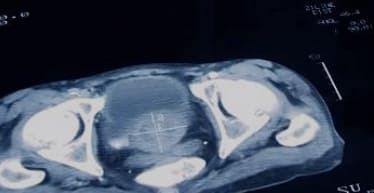

- 진단은 의사가 문진, 신체검사, 소변검사, 혈액검사, 초음파검사 등을 통해 진행합니다.